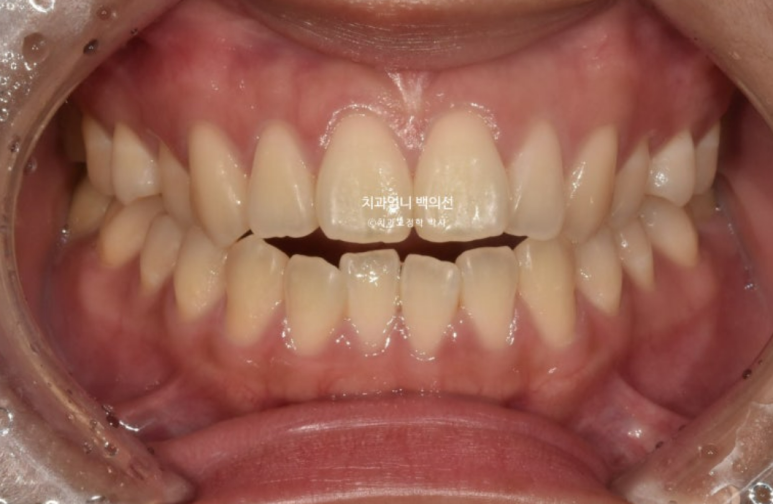

23.11

23년 11월 개방교합 치료를 위해 내원한 환자분입니다.

앞니 돌출감도 느끼는 상태입니다.

삐뚤한 치아 배열은 사랑니 공간을 이용해서 어금니를 뒤로 밀어내어 해결하기로 하고 앞니 개방교합은 어금니 함입을 통해 해결하기로 합니다.

어금니 함입은 입천장에 교정용 나사 미니스크류를 심어 도모하기로 합니다.

사랑니 공간으로의 후방이동 역시 미니스크류가 필요하죠.

악궁확장에 대해서는 악궁이 좁은 게 아니라 단순히 첫번째 작은어금니가 입천장으로 기울어진 상황이라 악궁확장은 따로 하지 않습니다.